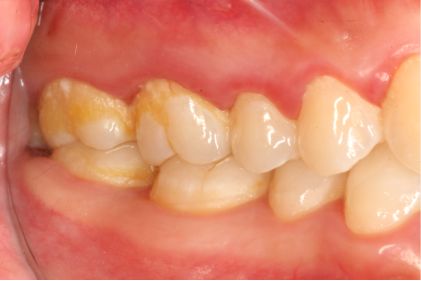

女,38岁,主诉牙龈出血1年,无系统疾病及药物过敏史。检查:牙列式18-27、37-47;18伸长,无咬合;口腔卫生欠佳,可见牙石、软垢,后牙区牙石软垢较多,全口牙龈边缘充血水肿,探诊出血阳性,牙周探诊深度3-4mm。诊断为慢性牙周炎(轻度)。

术前